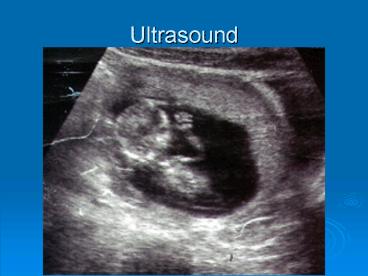

Use of ultrasound in mare reproduction

• Pregnancy as early as 10 days

• Twins

• Endometrial cysts

• Follicles

• Ovulation

• CL

• Ovarian tumors

• Uterine edema

• Uterine fluid

• Fetal heartbeat

• Fetal well being

• Fetal sexing

• Placental health

• Guided injection for aborting one twin

Ultrasound Images of Day 10 15 of Pregnancy

Ultrasonic Anatomy of Pregnancy